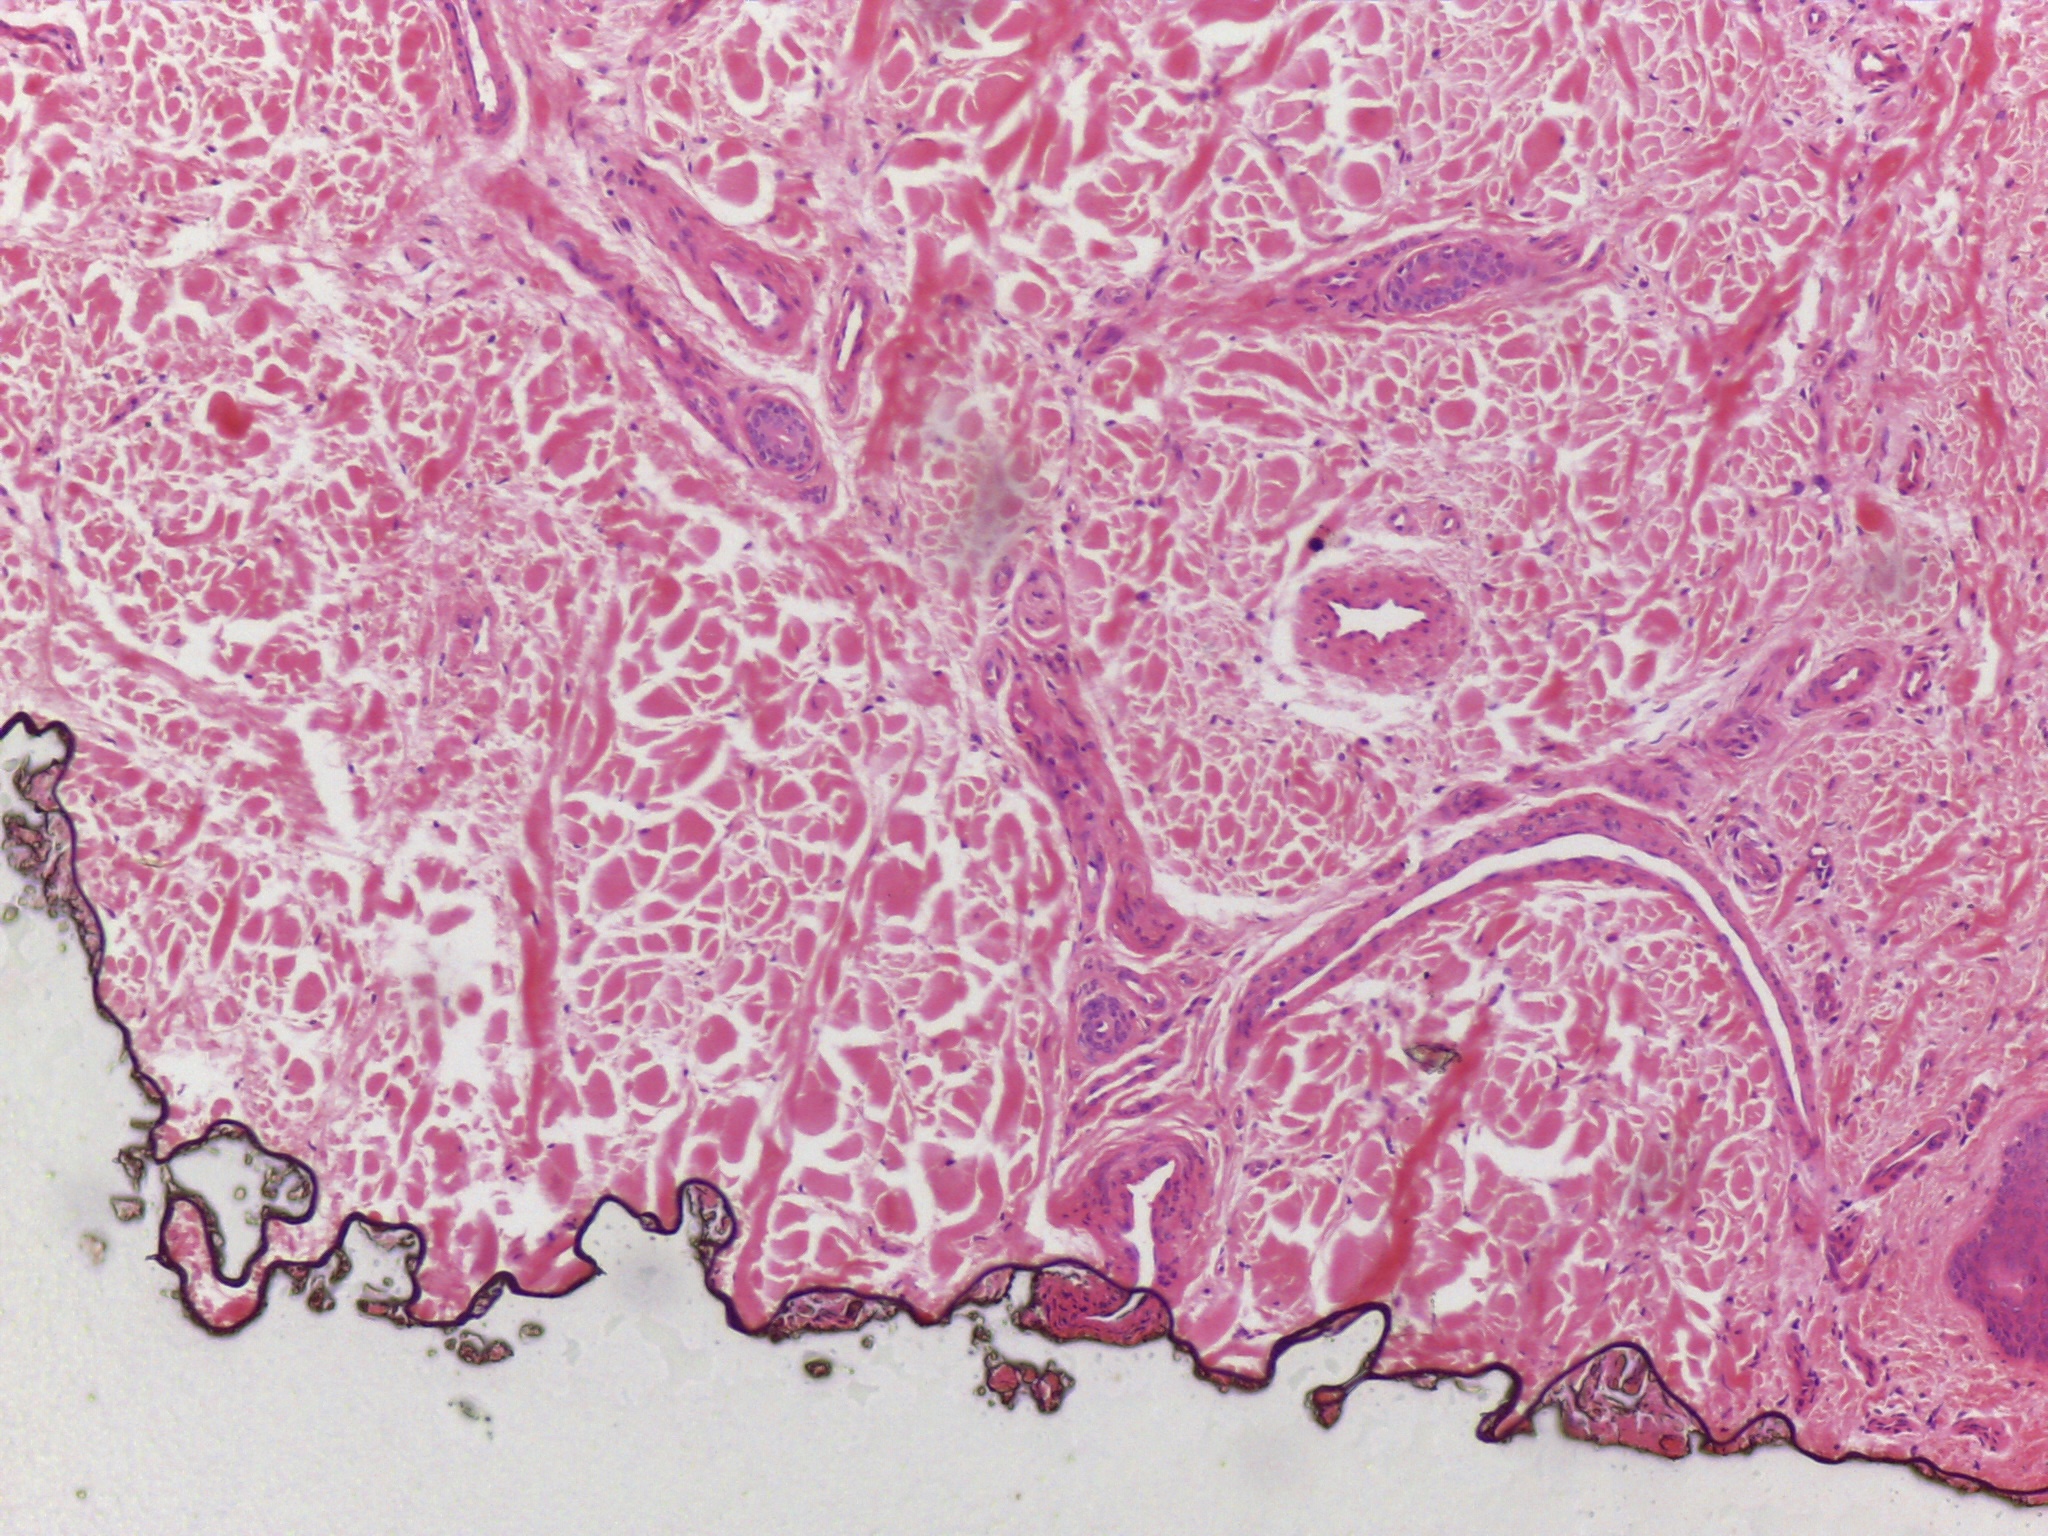

During my four years at university I have found myself being heavily influenced by science and biology, both of humans and plants, but more specifically on the skin and how much visual information can be contained within a single cell. I have been focusing my research on the skin condition vitiligo and the unusual patterns it creates on the body; I’ve always been confused and interested by the random patches so I began an exploration into how skin cells work and how this condition can be triggered. Through this I met some amazing scientists who inspired me through microscope imagery of the skin and lab experiments on the skin. I saw pinks, purples and blues, organic and uncontrolled structures contained within perfect shapes, and patterns hidden to the naked eye.

The imagery that I have gathered of these microscope images and of vitiligo patches has greatly inspired my work, as I have used similar colours and patterns and I have used techniques to try capture the randomness whilst making it controlled and perfected. Below are some of my own imagery that I have taken and some of my own paintings.